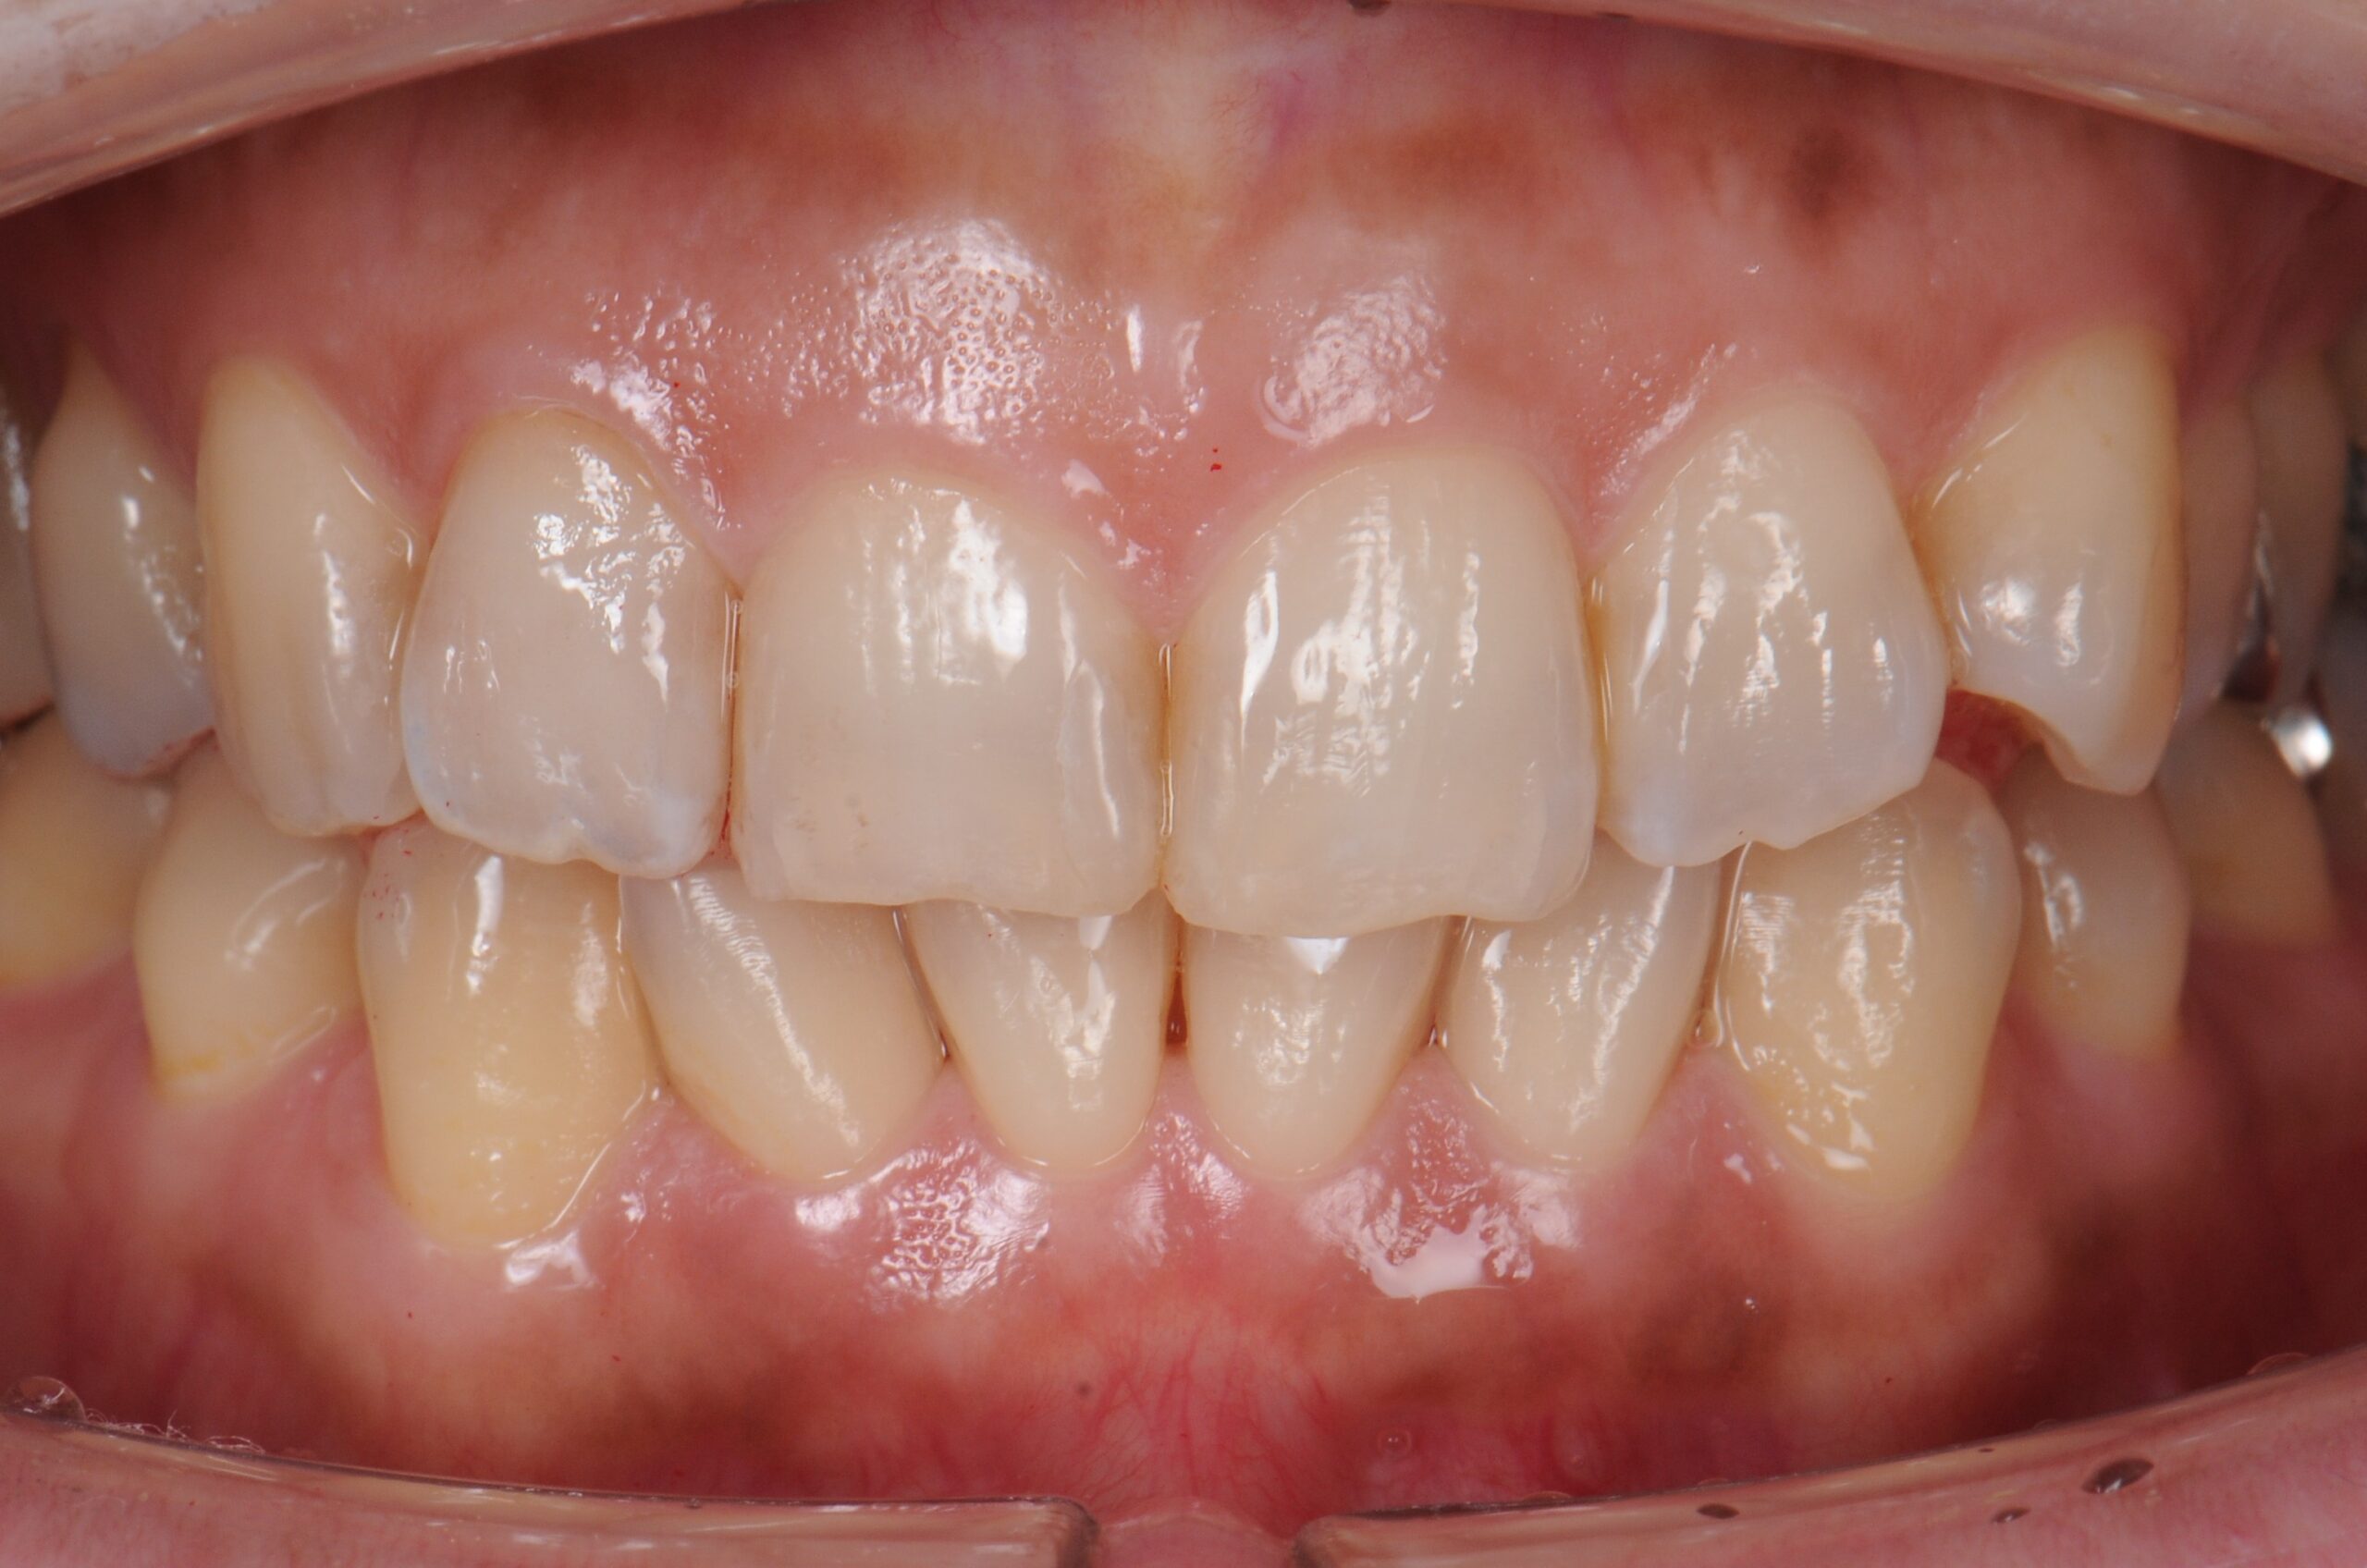

case1 症例(セラミッククラウン前歯)

治療前

| 費用(税込み) | 154,000円 |

|---|---|

| メリット・デメリット | デメリット 天然歯を削る必要がある。 |

| 治療回数 | 6ヵ月 |

| 主訴 | 前歯が黒い |